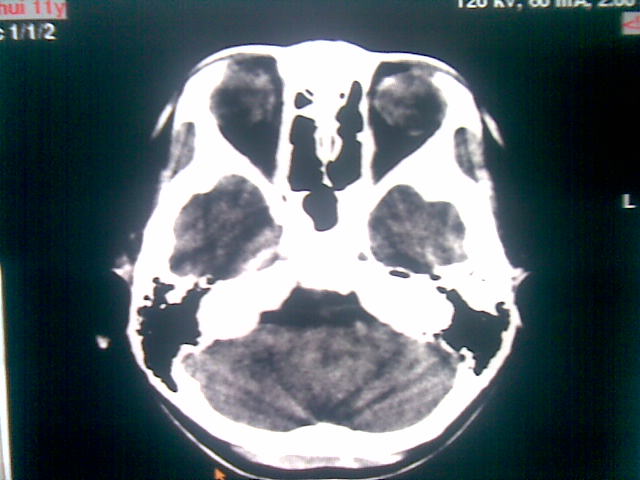

以下是引用随光逐影在2010-1-5 16:32:00的发言:[br]1)鞍上池囊性占位性病变,不排除蛛网膜囊肿可能;建议行mri检查。2)脑积水。

以下是引用yangyang2000在2010-1-5 20:41:00的发言:[br])鞍上池囊性占位性病变,不排除蛛网膜囊肿可能;建议行mri检查。2)脑积水